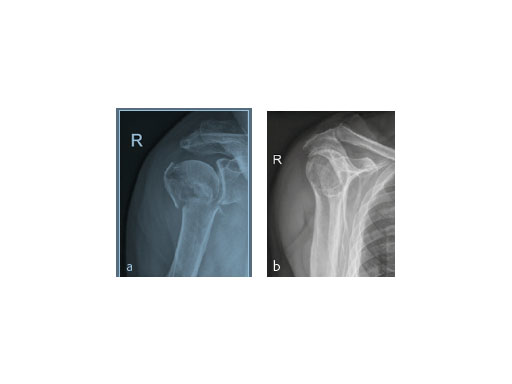

An 82-year-old male patient presented with a fracture dislocation of his right proximal humerus after a fall at home. Examinations revealed a highly unstable valgus-displaced 4-part fracture of the proximal humerus with a disruption of the medial hinge. No neurological injuries were evident (Fig 5).

The patient was placed in supine position, having the shoulder on two shoulder supports. After closed reduction of the shoulder, ORIF was performed via an anterior deltopectoral approach using the PHILOS. Four screws were augmented with Traumacem V+ under fluoroscopic control. Initially the treated shoulder was immobilized in a sling for 2 days followed by a pain-adapted functional treatment (Fig 6).